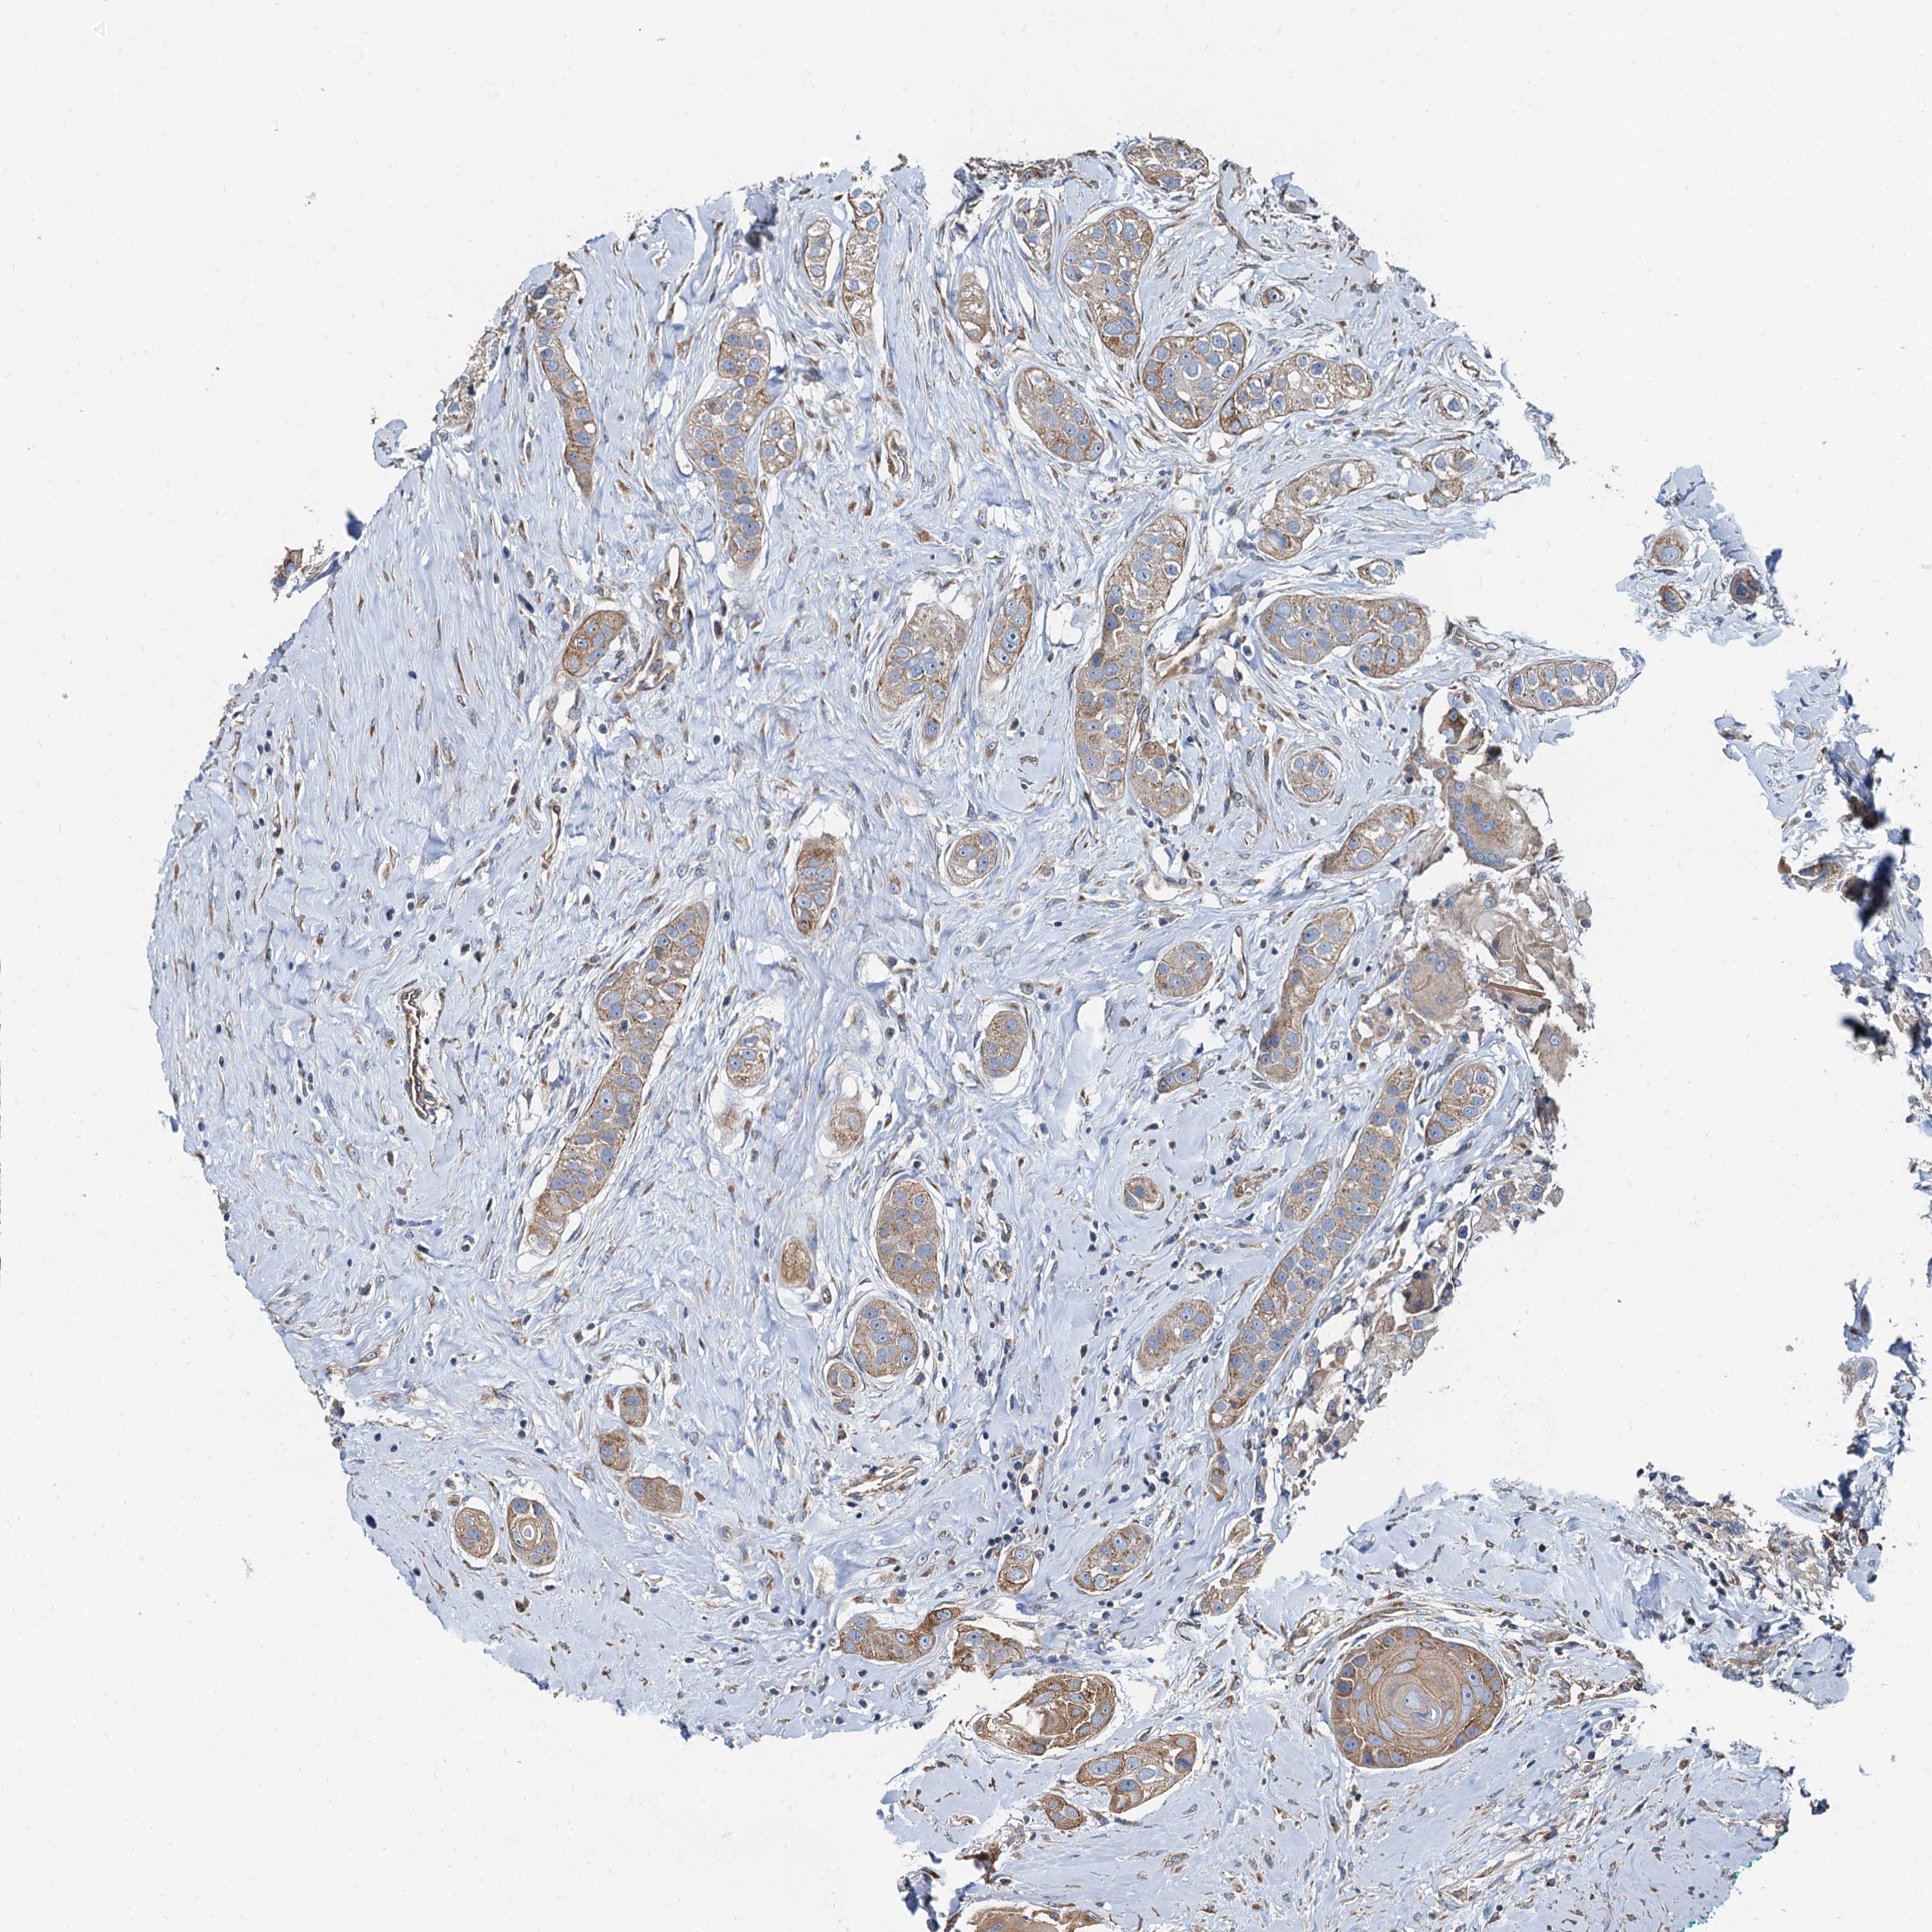

HEAD AND NECK CANCER - Protein expressioni

A mouse-over function shows sample information and annotation data. Click on an image to view it in a full screen mode. Samples can be filtered based on level of antibody staining by selecting one or several of the following categories: high, medium, low and not detected. The assay and annotation is described here.

Antibody stainingi

Antibody staining in the annotated cell types in the current human tissue is reported as not detected, low, medium, or high, based on conventional immunohistochemistry profiling in selected tissues. This score is based on the combination of the staining intensity and fraction of stained cells.

Each image is clickable and will lead to virtual microscopy that enables deeper exploration of all samples and also displays staining intensity scores, fraction scores and subcellular localization as well as patient and tissue information for each sample.

Antibody HPA076267

Staining

High

Medium

Low

Not detected

Intensity

Strong

Moderate

Weak

Negative

Quantity

>75%

75%-25%

<25%

None

Location

Nuclear

Cytoplasmic/membranous

Cytoplasmic/membranous,nuclear

Adenocarcinoma, NOS